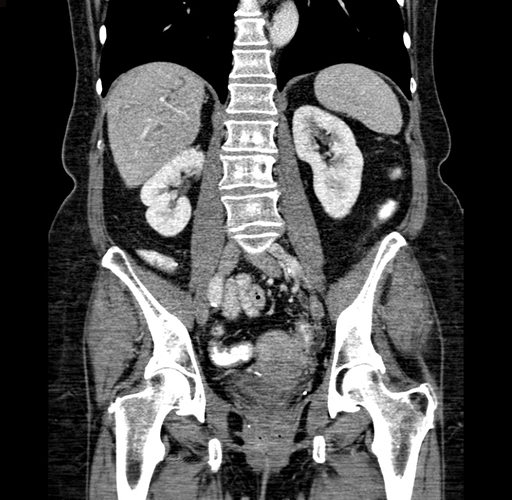

Pre-Chemo: Axial Venous

Pre-Chemo: Coronal Venous